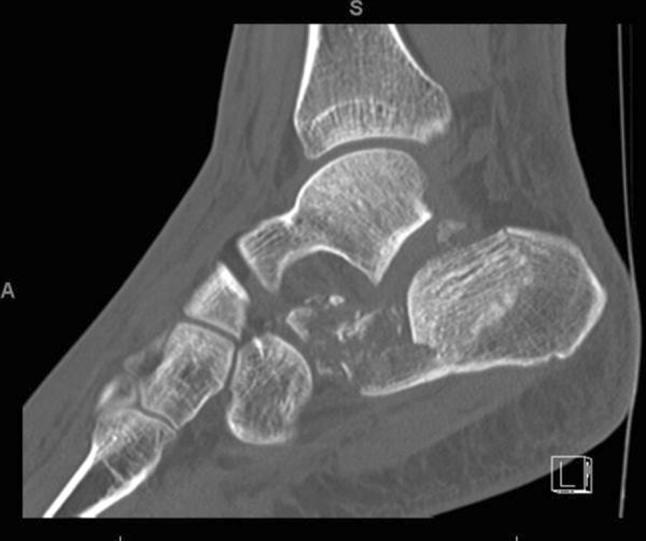

Calcaneal fractures: Where are we now?

This review article on the current management for calcaneal fractures discusses the advantages and disadvantages of different treatment options including the problems encountered. Controversies are described and the evidence reviewed. The management of some types of displaced intra-articular calcaneal fractures remains contentious; is there a preferred stabilisation method for each type of calcaneal fracture? How constant is the "constant fragment" in an intra-articular calcaneal fracture and what is the evidence for primary arthrodesis and what is its place in these fractures?